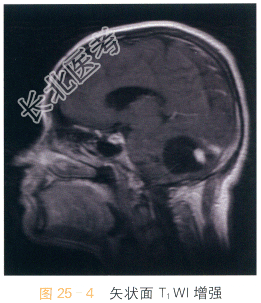

影像学资料如图25-1~图25-4所示。

读片分析:头颅横断面T₁WI示小脑半球囊性占位,呈低信号影,边界清晰,边缘光整,内可见附壁结节,呈等低信号影,第四脑室受压改变;横断面T₂WI囊液呈脑脊液样高信号影;增强扫描可见附壁结节明显强化。结合病史,患者考虑为血管母细胞瘤。